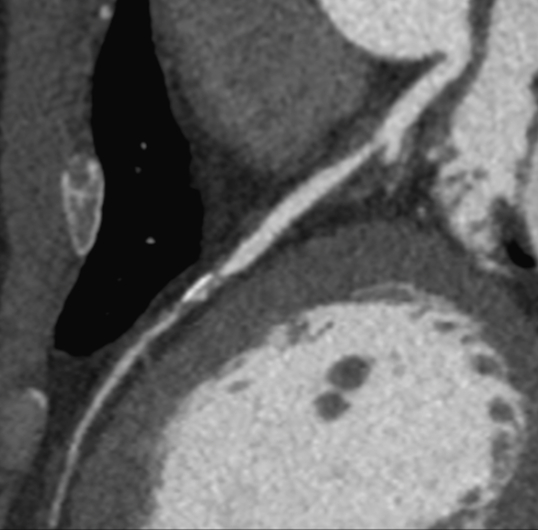

En cardiovasculaire, le CHU de Rouen est reconnu au plan national pour l’exploration du cœur par le scanner et l’IRM. L’unité d’imagerie cardiovasculaire est partie prenante de l’Institut Alain Cribier des Valves Cardiaques et de la plateforme de recherche MiraclAI. Nous disposons de matériels haut de gamme et d’une équipe médicale et para médicale étoffée attirant de nombreux étudiants. Les thématiques de recherche incluent les maladies valvulaires cardiaques et l’étude des cardiomyopathies, notamment la Maladie de Fabry.

• Le scanner: Nous pratiquons le scanner pour le dépistage et le traitement de la maladie coronaire, pour le bilan pré opératoire des valvulopathies aortiques (TAVI notamment) ou mitrales, des aortopathies thoraciques et abdominales ou pour le suivi des cardiopathies congénitales. Dans le domaine de la prévention cardiovasculaire, le score calcique est disponible sur les sites de Charles-Nicolle et Bois-Guillaume.

Scanner sarcoidose